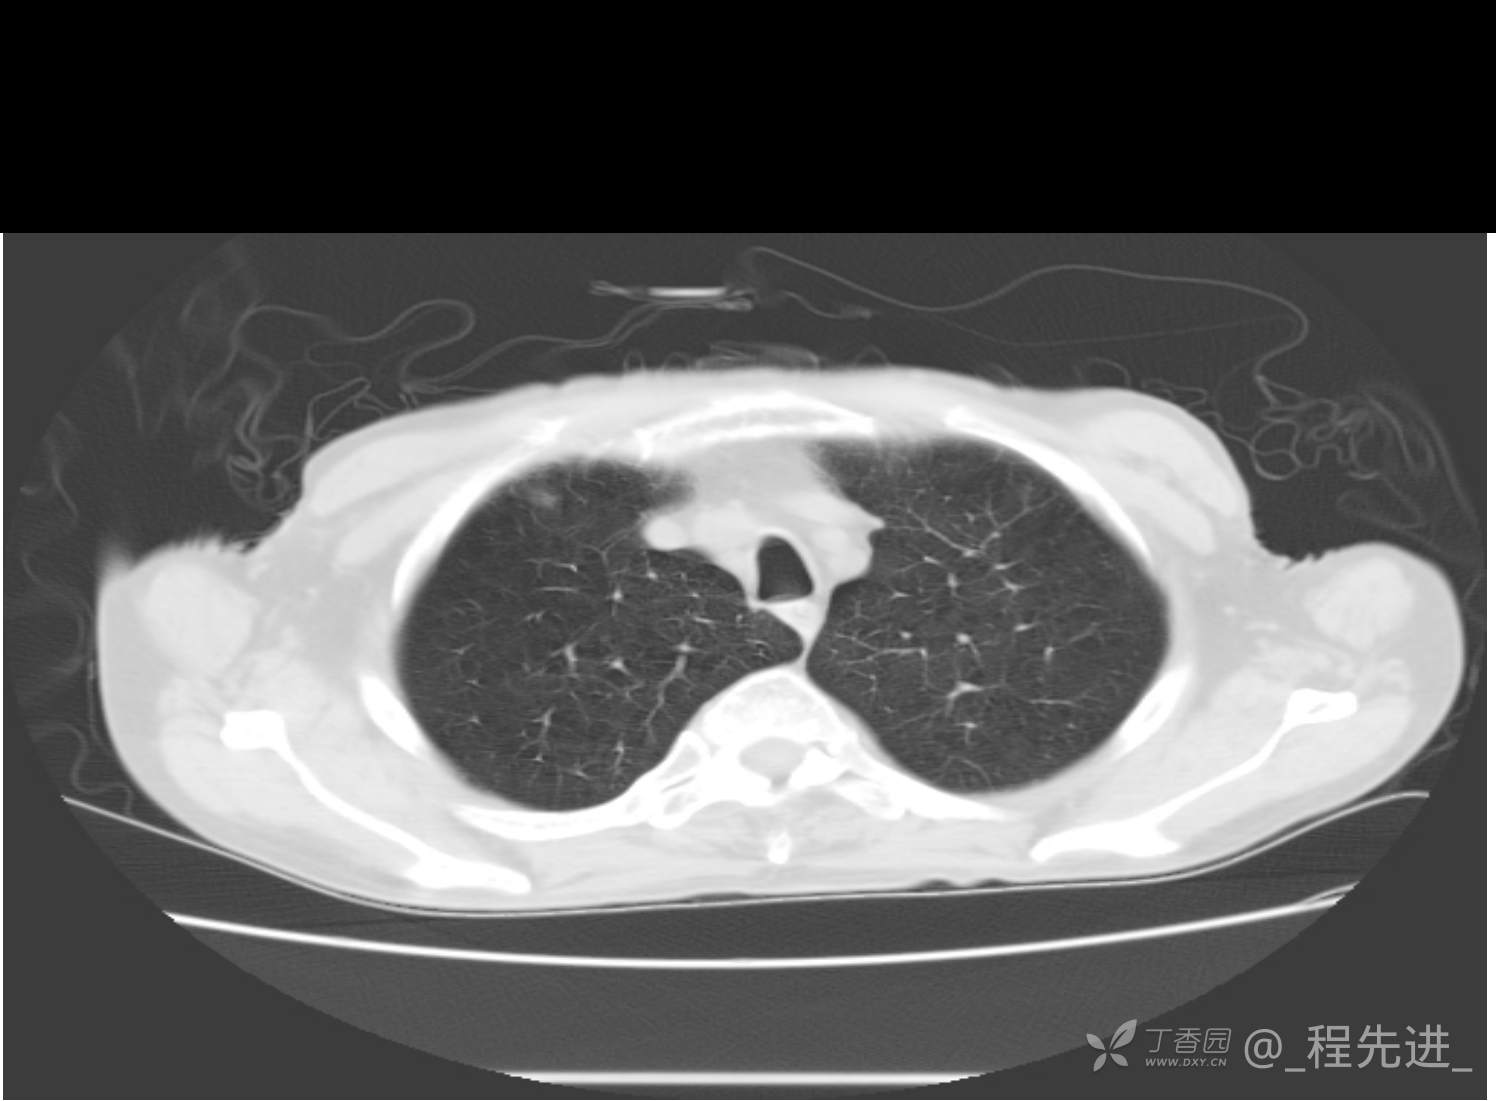

患者性别:男

患者年龄:81岁

简要病史:反复咳嗽、咳痰20余年,加重1周。两肺呼吸音低,可闻及散在干湿啰音。